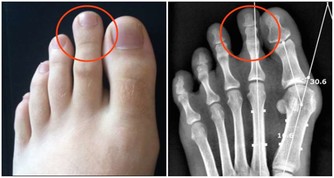

(2)痛風患者/高尿酸血症

豆腐中含嘌呤較多,對嘌呤代謝失常的痛風病人和血尿酸濃度增高的患者,需要控制豆腐等高嘌呤食物的攝入。